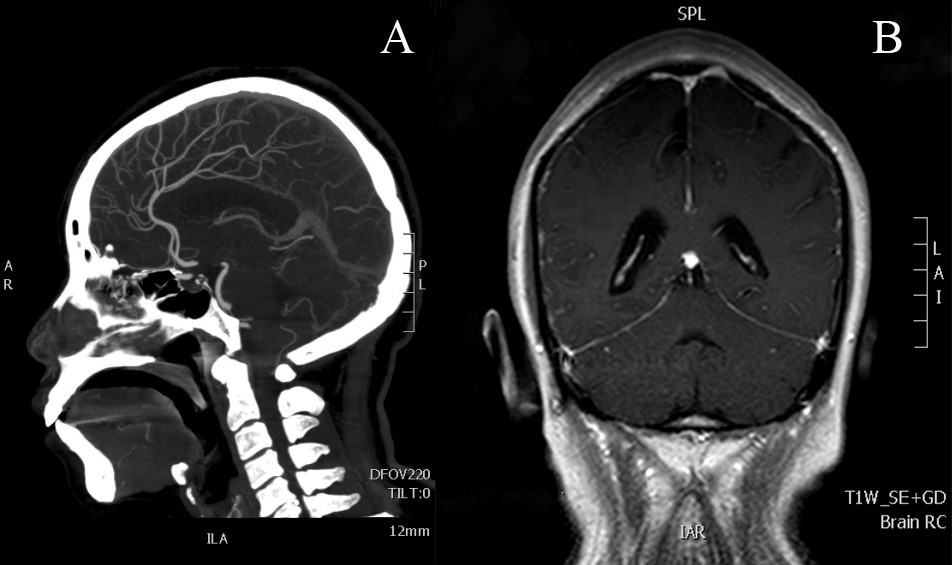

To investigate the cause of increased ICP, gadolinium-enhanced brain magnetic resonance imaging (MRI) revealed diffuse meningeal enhancement. Moreover, computed tomography angiography revealed no significant abnormalities (Figure 2). These findings ruled out intracranial tumors, cerebral pseudotumors, and intracranial venous sinus thrombosis as causes of intracranial hypertension. A lumbar puncture was subsequently performed, and CSF flow analysis revealed a pressure of 28 cm H2O with normal glucose and protein levels. CSF cytopathological analysis revealed malignant cells with karyoplasm ratio imbalance, double nuclei, and abnormal division (Figure 5).

Figure 2 Brain neuroimaging examination

(A): Computed tomography angiography (CTA). (B): Gadolinium-enhanced brain magnetic resonance imaging (MRI). CTA showed no significant abnormalities. MRI revealed diffuse meningeal enhancement.